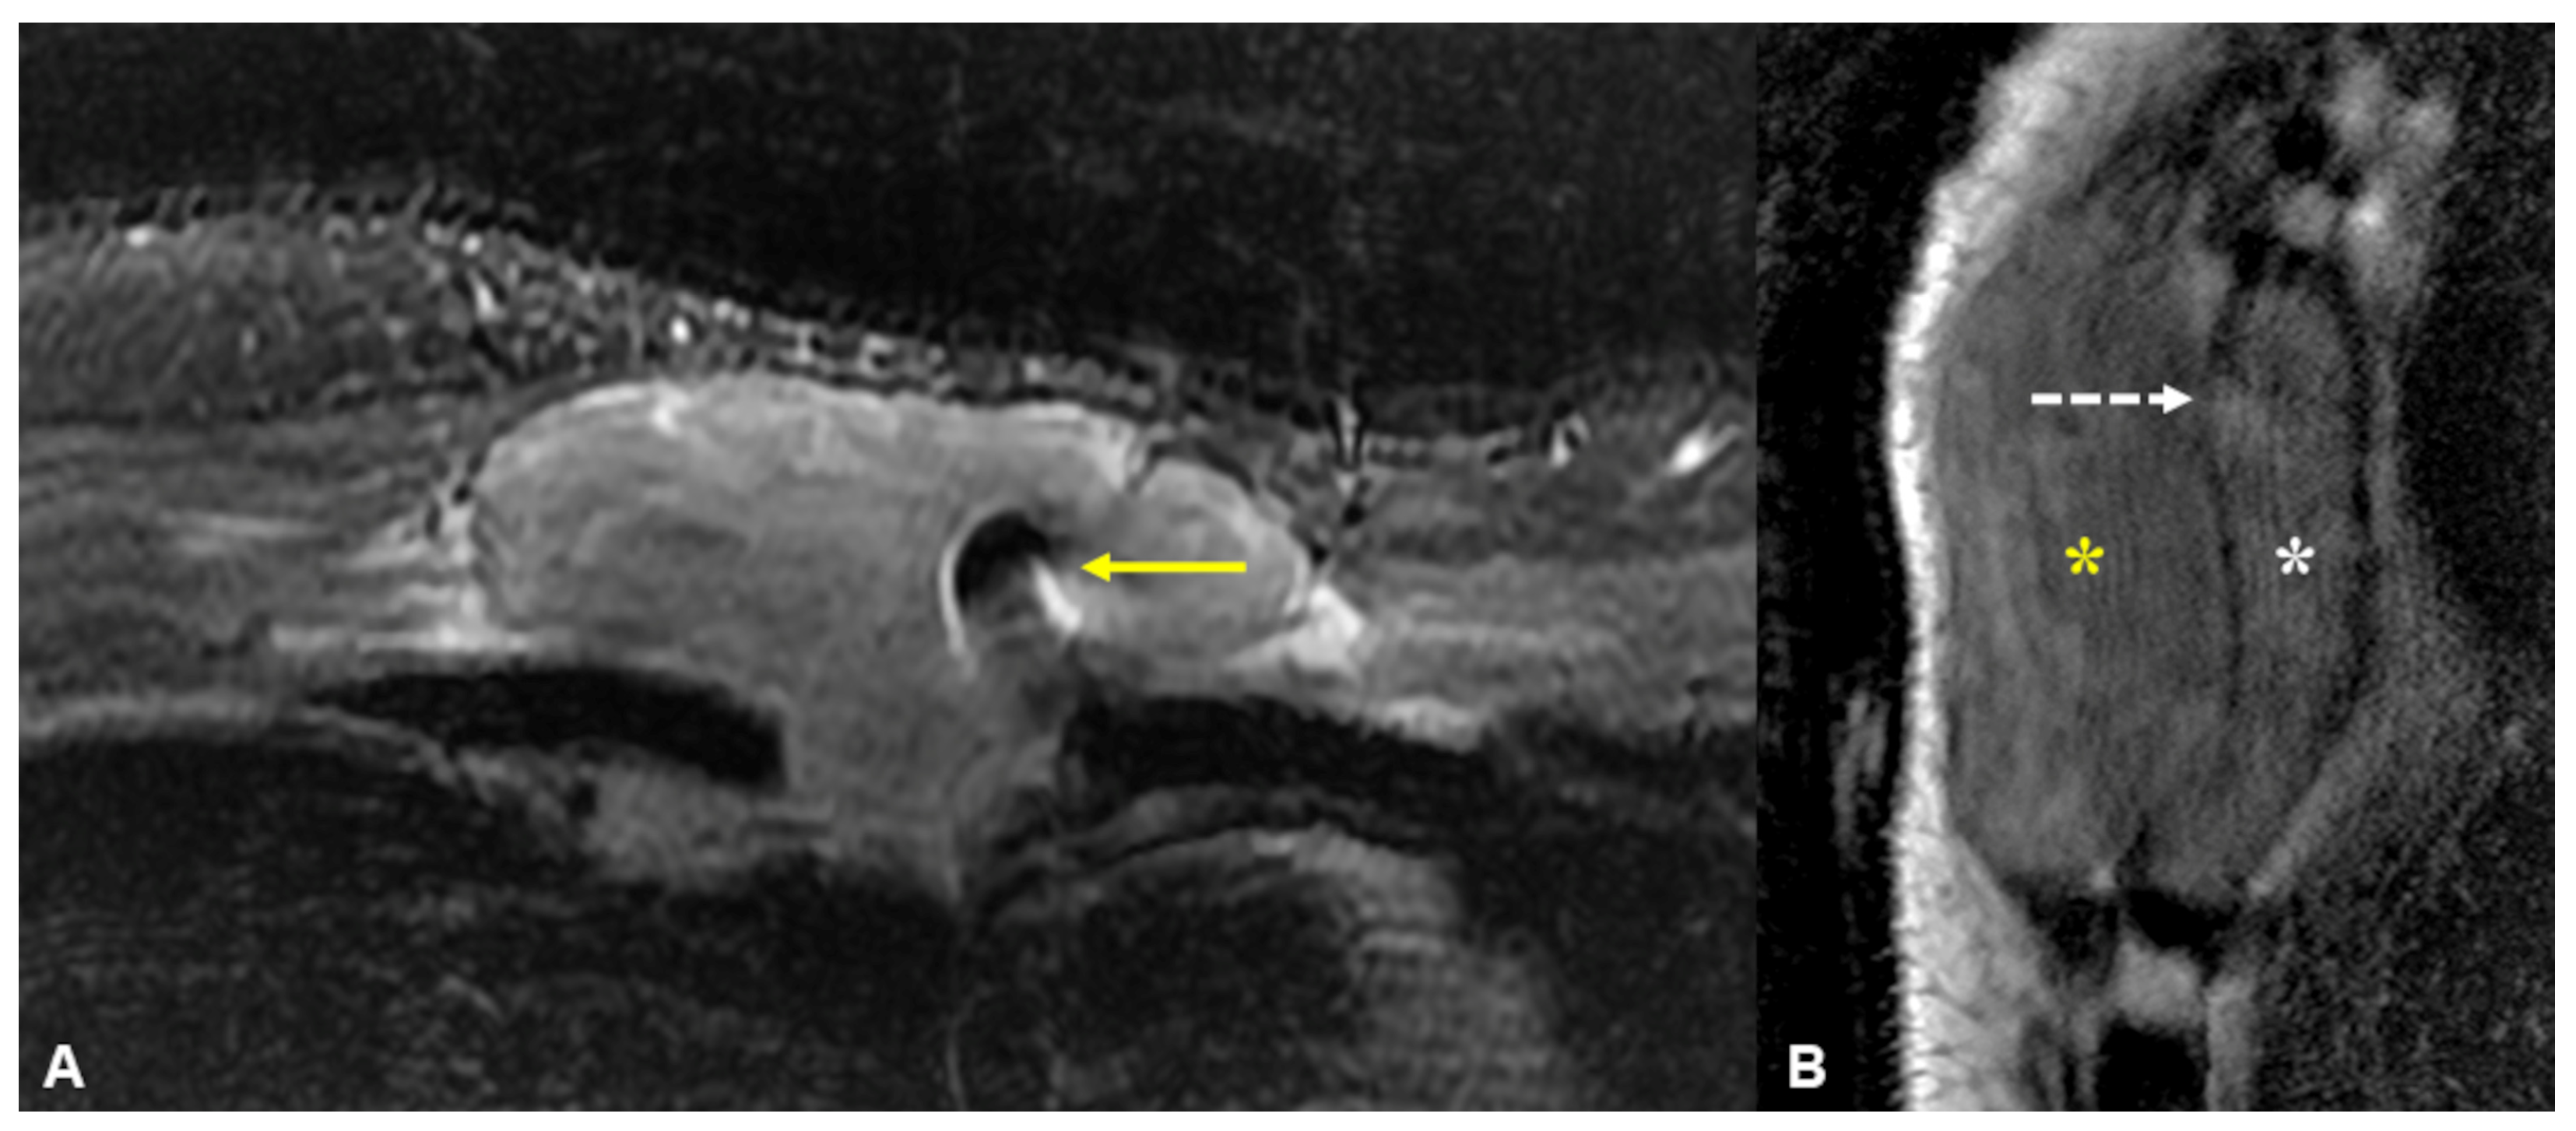

Targeted ultrasonography of the anterior chest wall shows a heterogeneous hypoechoic 7.95 cm mass encasing the sternal wires, which are seen as linear hyperechoic structures indicated by the yellow arrows. The sternum’s haematopoietic marrow and rich blood supply serve as ideal substrates for the development of tumours and infections. The majority of sternal lesions are malignant [1], with metastases being most common in adults.